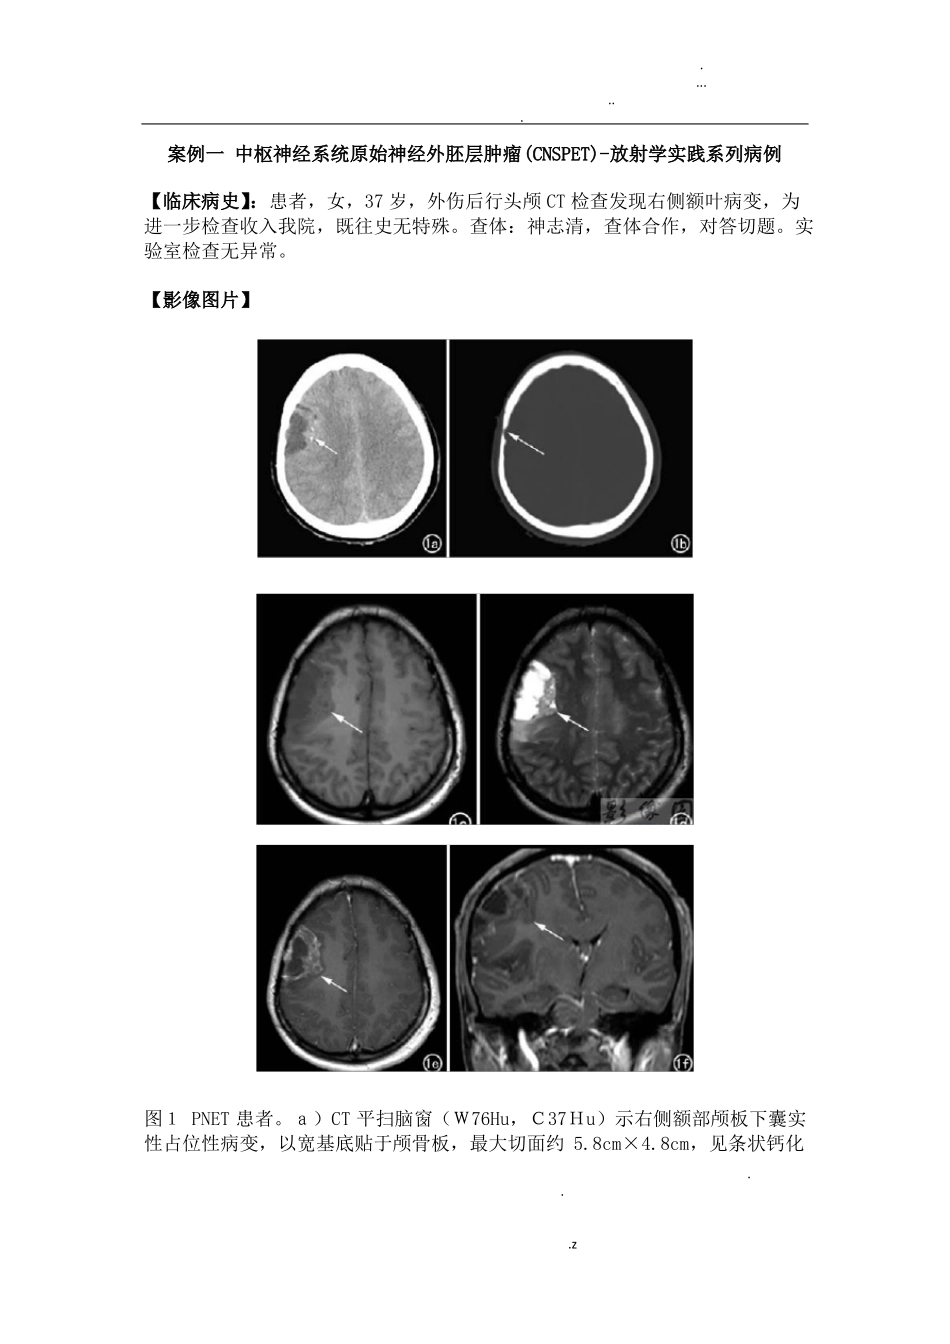

.......案例一 中枢神经系统原始神经外胚层肿瘤(CNSPET)-放射学实践系列病例【临床病史】:患者,女,37 岁,外伤后行头颅 CT 检查发现右侧额叶病变,为进一步检查收入我院,既往史无特殊。查体:神志清,查体合作,对答切题。实验室检查无异常。【影像图片】图1 PNET 患者。a)CT 平扫脑窗(W76Hu,C37Hu)示右侧额部颅板下囊实性占位性病变,以宽基底贴于颅骨板,最大切面约 5.8cm×4.8cm,见条状钙化...z.......(箭);b)骨窗(W2000Hu,C600Hu)示邻近颅板骨质变薄(箭);c)轴面 T1WI(TE 15ms,TR 487ms)示右额部颅板下囊实性肿块(箭),实性部分呈等信号,囊性部分呈低信号;d)横轴面 T2WI(TE 110ms,TR 3985ms)示病灶实性部分呈等、偏高信号,囊性部分呈高信号,灶周可见轻度水肿(箭);e)横轴面 T1WI 增强扫描示病灶呈不规则厚壁环形强化(箭),囊性部分无强化;f)冠状面 T1WI 增强扫描示病灶呈不规则环形强化,囊性部分无强化(箭);g)病理图示肿瘤由致密的小圆细胞构成,细胞核深染,核仁不明显,细胞密集。【影像表现】:CT 检查:右侧额部颅板下囊实性占位性病变,最大切面约5.8cmX4.8cm,见条状钙化,病灶以宽基底贴于颅骨板并邻近颅板骨质变薄,侧脑室受压,中线结构轻度左移(图 a-b)。MRI 检查:右额部颅板下囊实性肿块,实性部分呈等 T1、长 T2信号,灶周轻度水肿,增强扫描呈不规则厚壁环形强化(图 c~f)。【手术所见】:右额下回后方一实性肿物,其基底为脑表面,大小约5cmX5cm,质软,色暗红,血供丰富,无包膜,见肿瘤突出脑皮层表面并向四周硬膜下腔延伸,肿瘤侵入脑达3cm,与正常脑组织分界不清。【病理结果】:考虑为中枢神经系统原始神经外胚层肿瘤(PNET)(图1g)。【讨论】:原始神经外胚层肿瘤(PNET)是一类由原始神经上皮细胞衍化而来的高度恶性肿瘤,侵袭性强、预后差。发生在幕上的 PNET 极为少见,仅占整个颅脑肿瘤的0.1%左右,约85%的患者为儿童,成人发病者更为罕见。2007 年 WHO将中枢神经系统胚胎性肿瘤中的幕上原始神经外胚层肿瘤 (SPNET)以及位于脑干、脊髓的类似肿瘤归于一类,并改称为中枢神经系统原始神经外胚层肿瘤。病理上肿瘤实质由类似胚胎神经管原始未分化细胞构成,细胞密度高,胞外水含量低,核分裂易见,Homer Wright 假菊形团块样结构为其特征性表现,可伴有出血、坏死,免疫组化检测示瘤细胞NSE、CgA、Syn、Vim...